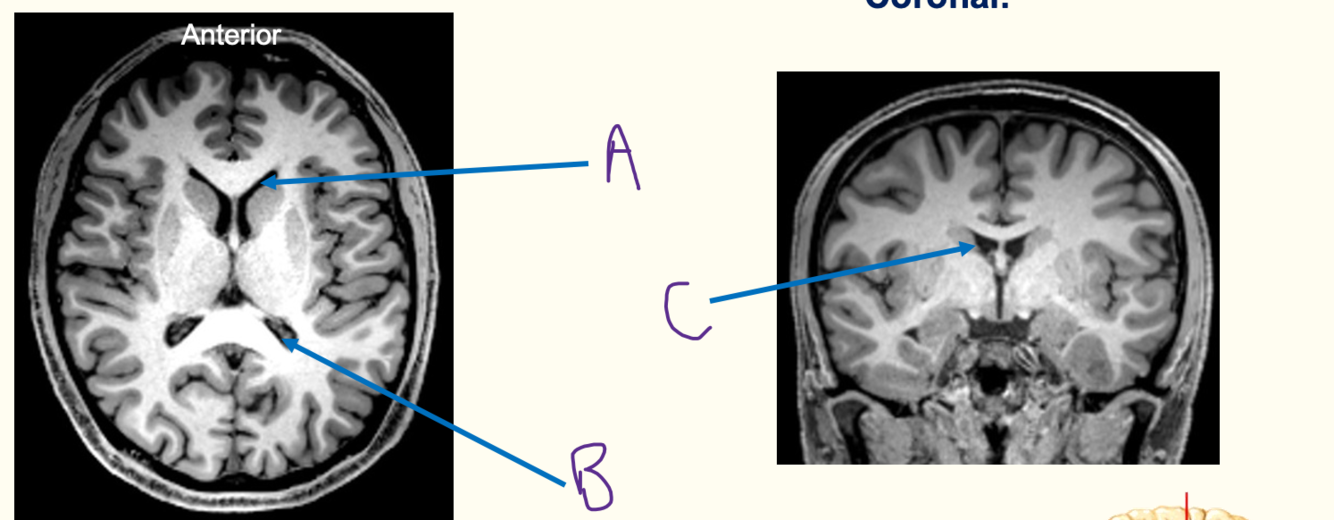

iv) label diagram A-C

iv) A = anterior horn

B = posterior horn

C = body

v) septum pellucidum seperates the lateral ventricles

vi) corpus callosum sits in roof

vii) caudate nucleus sits in the lateral wall

viii) hippocampus sits in the floor of the inferior horn